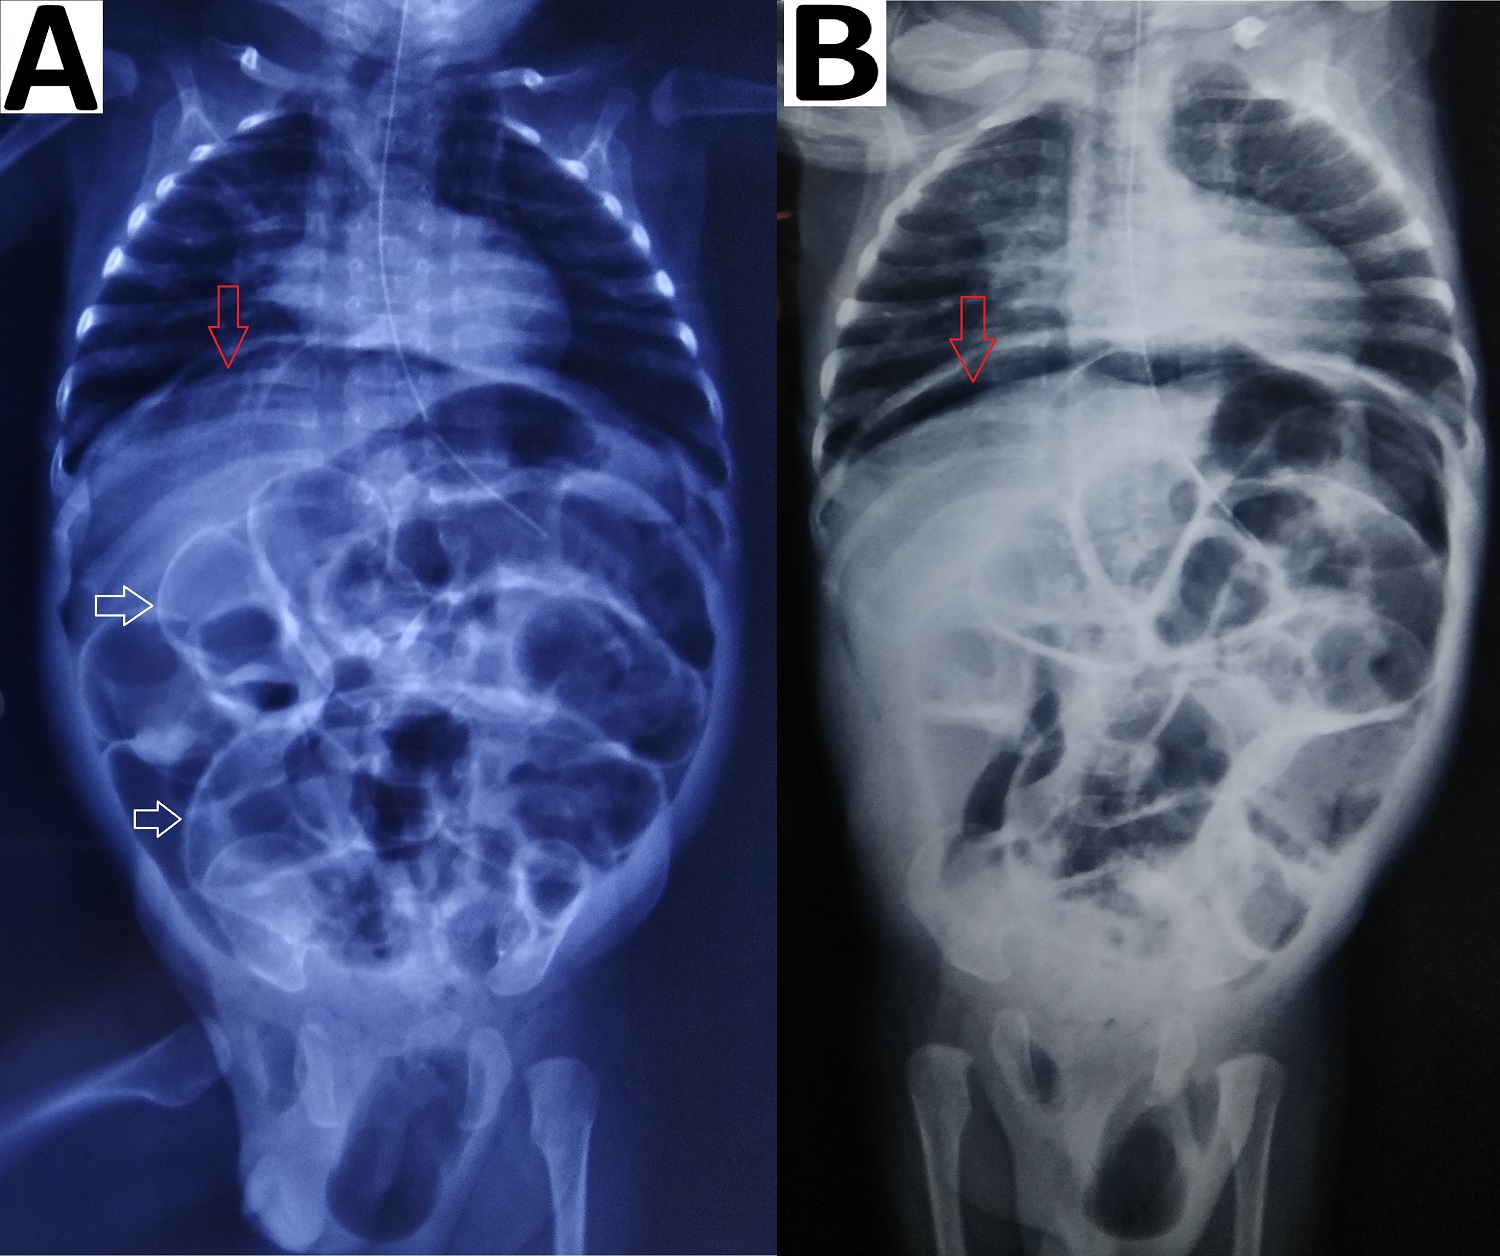

Figure 3

Abdominal radiographs (erect) (A) showing gas under the diaphragm (red arrow), Rigler sign (white arrows); supine image (B) showing pneumoperitoneum (red arrow) and pneumoscrotum (yellow arrow).

Pneumoperitoneum with air under both the domes of the diaphragm was seen in all 4 patients on erect abdominal radiographs (Fig. 1)(Fig. 2)(Fig. 3)(Fig. 4). There was an absence of free fluid in the peritoneal cavity evident by the absence of air-fluid level in the peritoneal (abdominal) cavity i.e. outside bowel loops in all the patients. Dilated small bowel loops were seen in 3 out of 4 patients. Rigler sign or double-wall sign was present in 3 patients. Radiographic evidence of pneumothorax (simultaneously present with pneumoperitoneum) was seen in 1 patient (Fig. 4). Pneumoscrotum was appreciated in 2 patients (Fig. 3)(Fig. 4).

Pneumoperitoneum in a neonate is classically due to GI perforation and necrotizing enterocolitis (NEC).[3], [4] Pneumoperitoneum is usually diagnosed by an erect abdominal radiograph showing free air under the domes of the diaphragm. In the neonates the other radiographic signs include, (a) rounded or oval lucency over the upper abdomen in the supine position, (b) increased lucency i.e. triangular or a semilunar collection of air anterior to the abdominal viscera or above the liver in lateral decubitus position, (c) large volume of free air may give rise to the football sign, where the air outlines the whole of the peritoneal cavity and under the surface of the diaphragm, (d) the lacing of the football i.e. outlining of falciparum ligament of the liver against the radiolucency of free abdominal air on supine view [4], [5], [6] (e) Rigler sign or double-wall sign is free gas on both sides of the bowel wall,[4], [5] (f) pneumoscrotum has been explained due to presence of patent processus vaginalis and passage of air from the peritoneal cavity into the scrotum.[3], [5], [6]